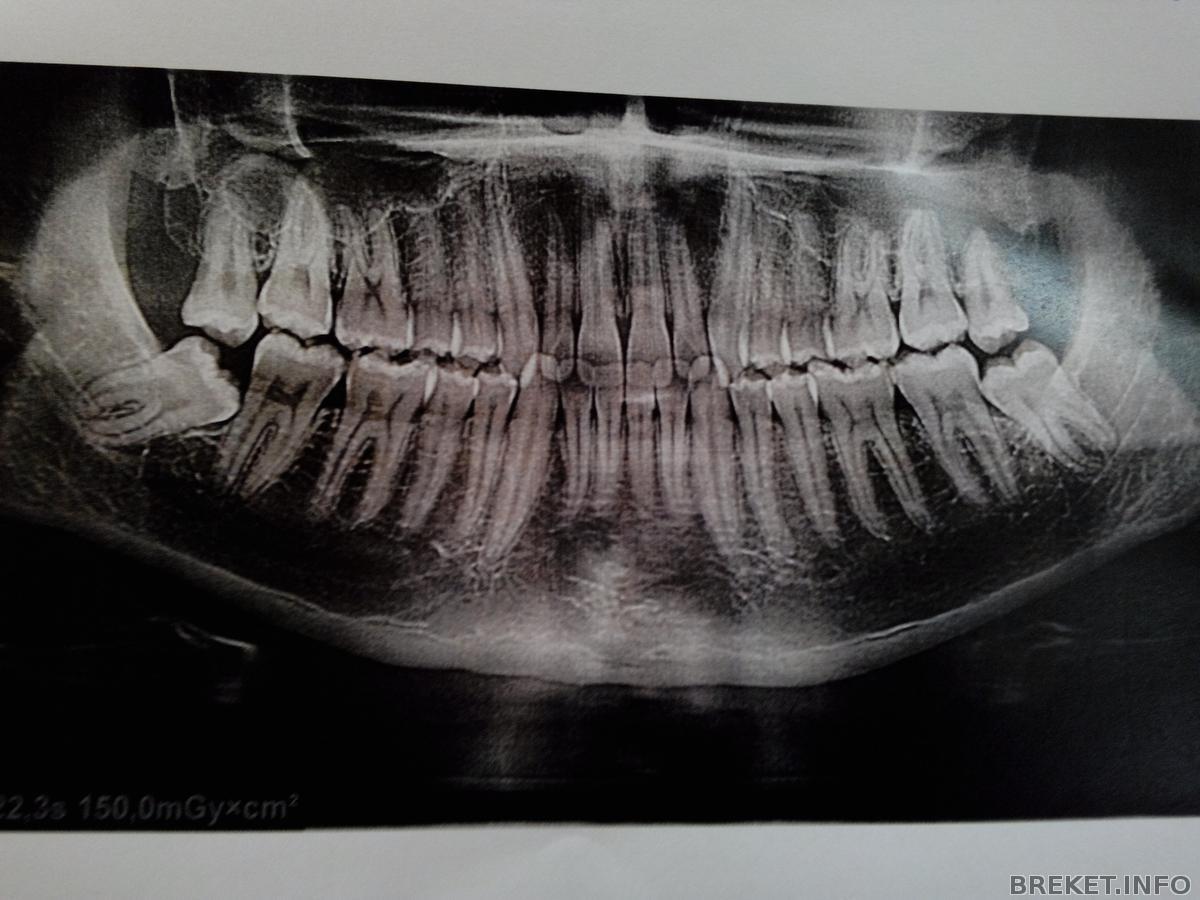

вот его снимок, даже не знаю как уболтать) наверное пока не реально припечет- добровольно не пойдет)) ваши мужчинки молодцы, что решились)))